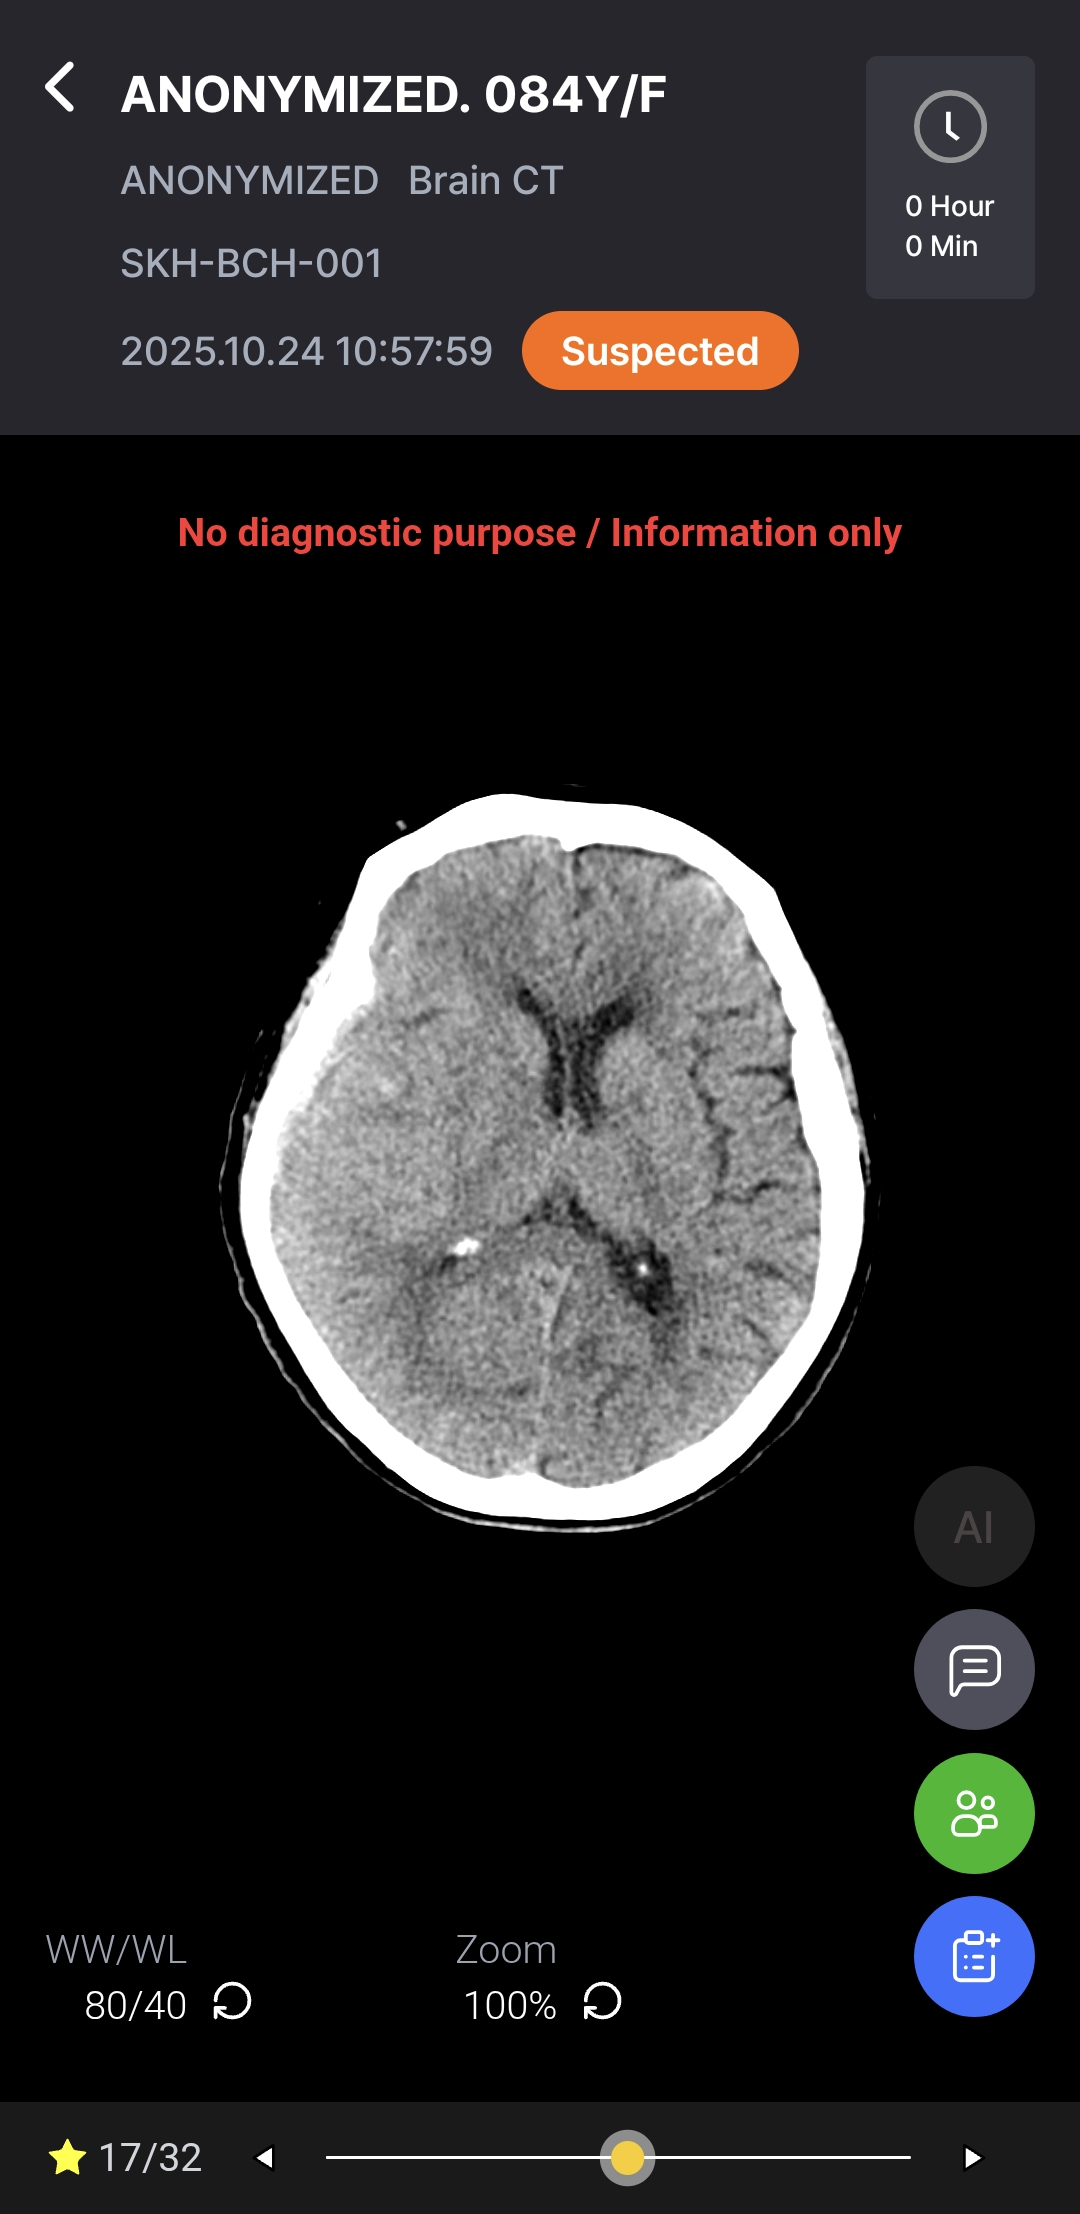

Download BrochureAI-powered diagnostic support for rapid, accurate detection and localization of brain hemorrhages on non-contrast CT, with ROI visualization and volume quantification to help radiologists assess hemorrhagic regions.

Notifications & AI DICOM Viewer